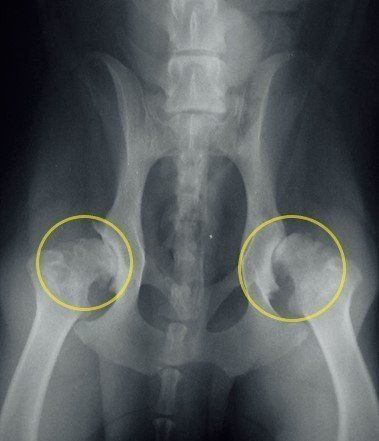

症状があらわれている大腿骨のエックス線写真。

初期のうちはエックス線写真でも判断しにくい場合があるため、少しでも気がかりなことがある場合は、かかりつけ医に相談してみるとよいでしょう。